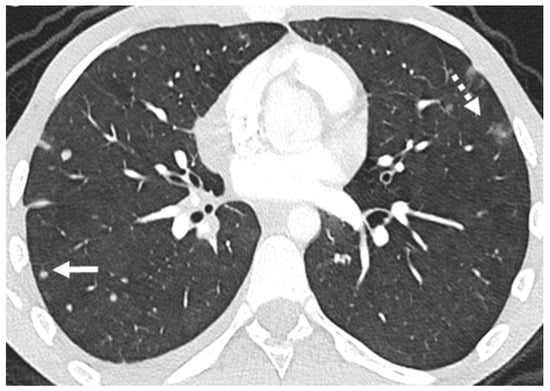

2.1. Parenchymal Metastasis